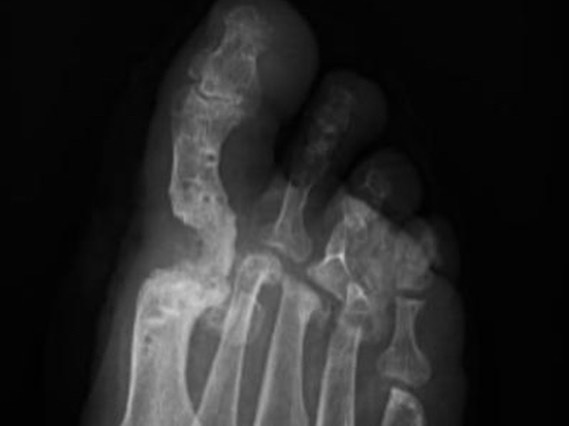

- Pseudartrosis: Ocurre cuando un hueso fracturado o una articulación fusionada no se consolida correctamente, es decir, no se une como debería. En el caso de la artrodesis de hallux, una pseudartrosis significa que la articulación no se fusionó por completo, lo que puede causar dolor y limitar la movilidad.

Cuando una artrodesis de hallux no se consolida, es necesario realizar una cirugía de rescate para corregir la pseudartrosis. Esta cirugía implica limpiar el área, eliminar cualquier tejido que impida la consolidación y, en algunos casos, utilizar injertos óseos o factores de crecimiento para estimular la unión ósea.